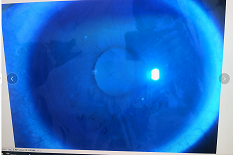

圓錐角膜要做那種治療比較好

瘢痕期:角膜急性角膜水腫、混濁,消退后基質層殘留瘢痕。